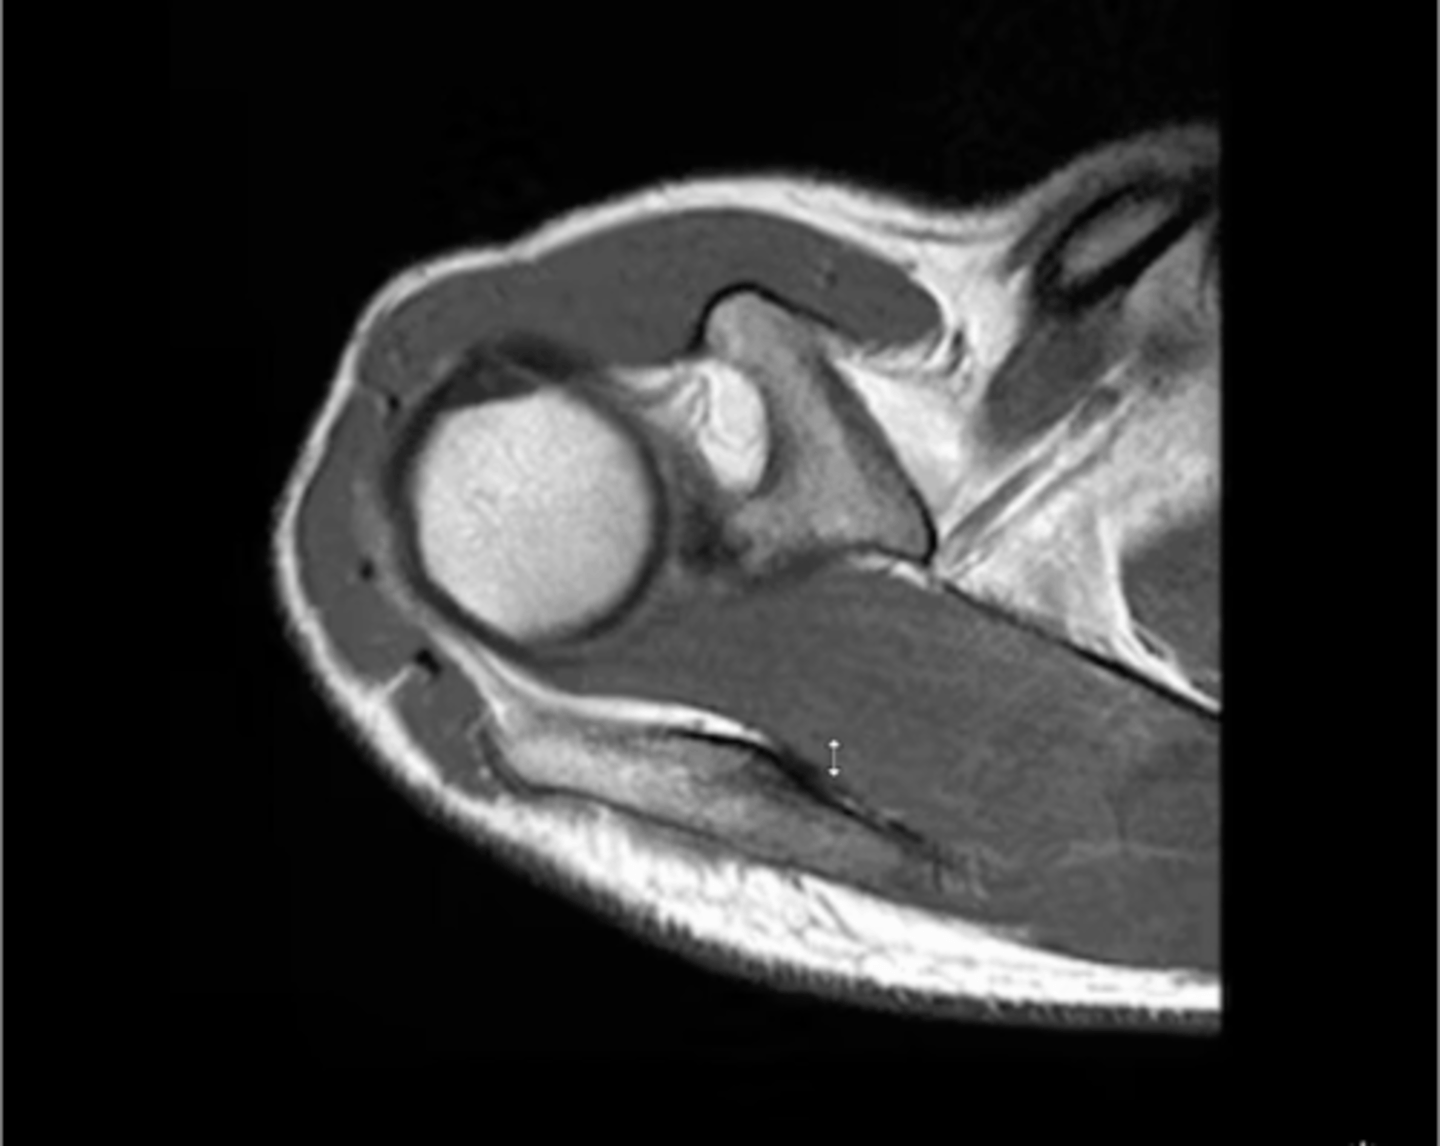

MORE fatty atrophy and infiltrate -- this is a prognostic factor for patients! (i.e., we DON'T want to repair a cuff that already has a ton of fatty infiltrate)

What is this image depicting? Why is it important?